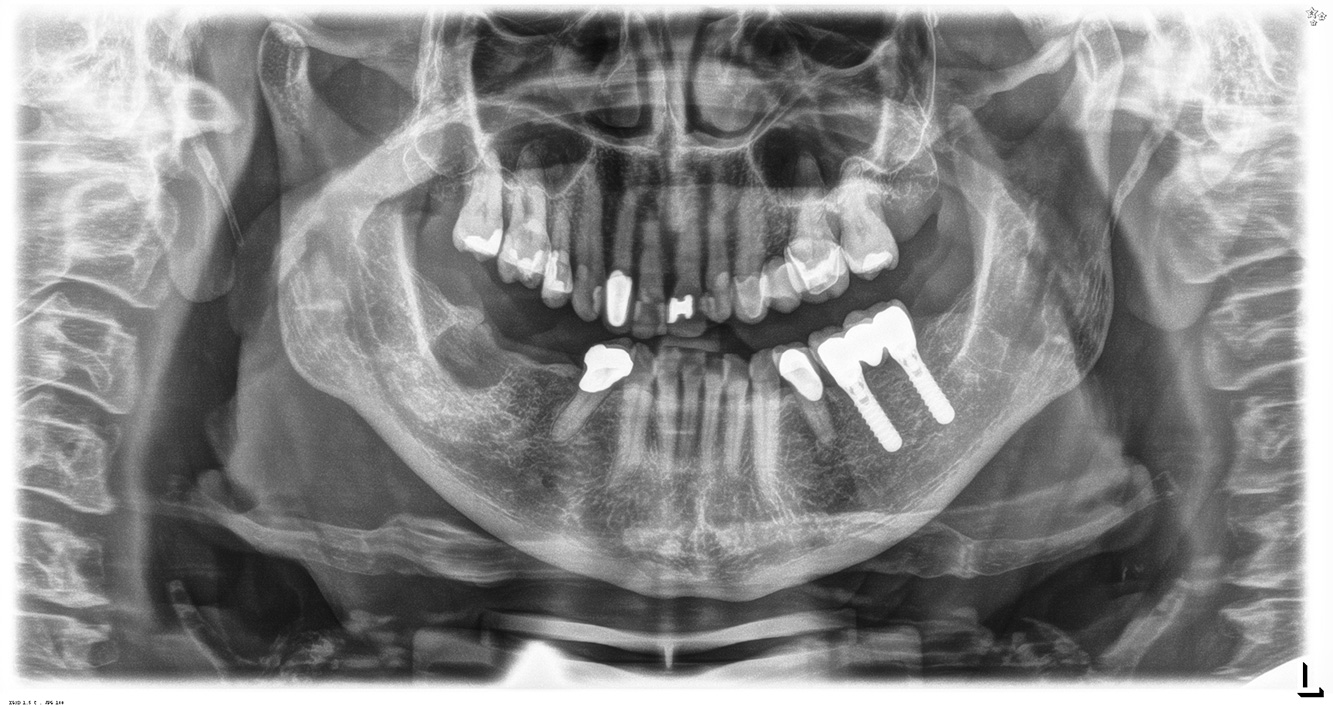

The 68-year-old patient has no general health conditions and is not taking any medication that may be relevant to her oral health, and her lifestyle does not pose any particular risk. The patient has two dental implants (3rd quadrant, for five years) and a previous case of periodontal disease (stage IV, grade B periodontitis) with tooth loss. Currently the periodontal conditions are stable. However, periodontitis significantly increases the biological complications of implantations and there is a risk of implant loss (21). Four recommendations can be determined for the prophylaxis session.

Because the patient has implants and a history of periodontal disease, she is at risk of developing peri-implantitis. It is therefore recommended that she attend a recall session every three to four months.